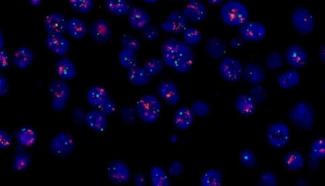

MF43-N荧光显微镜搭配MC50-S相机,可精准捕捉荧光标记的DNA探针信号,高效检测乳腺癌、宫颈癌等疾病中的基因扩增或缺失,助力个性化诊疗。

MF43-N+MC50-S搭配四波段光源拍摄的FISH图像